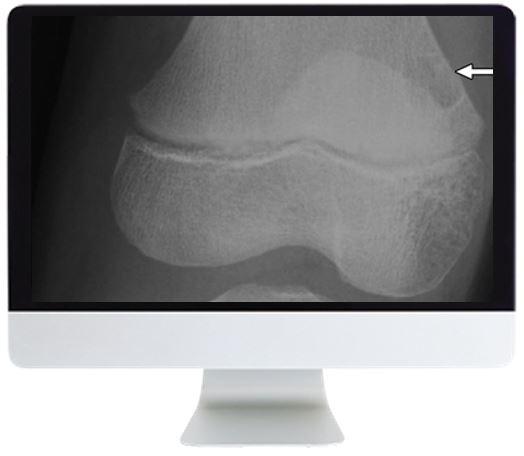

ARRS Clinical Case-Based Review of Musculoskeletal Imaging 2019

Focus on honing your diagnostic skills with this distinctive Online Course that combines didactic lectures and rapid-fire case review sessions to provide deeper insights into musculoskeletal imaging.

- Knee Trauma – Menisci—Daniel E. Wessell, MD, PhD

- Trauma—Ambrose J. Huang, MD